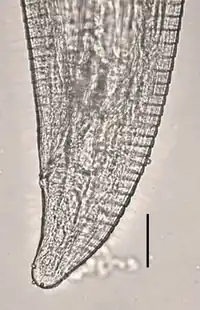

Morphology

As with most Thelazia worms, they are small parasites that average about 12-13 mm long.[1] To differentiate between other members of this genus, T. californiensis has a vulva that opens mid-ventrally, while T. callipaeda has an anterior vulva.[1]